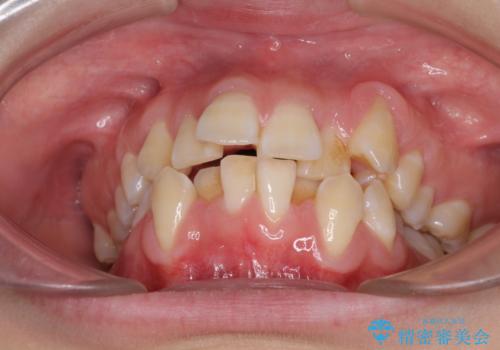

- 上下前歯の叢生と八重歯を気にして来院された患者様です。

前歯部叢生のスペースを獲得するため、上下顎左右小臼歯各1歯を抜歯することとしました。